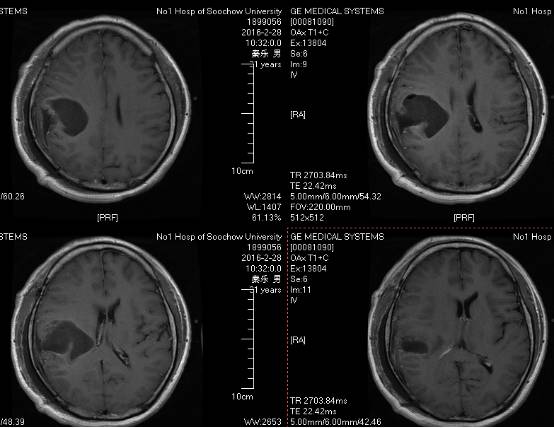

术后患者恢复良好,神志清,精神佳,四肢肌力V级,肌张力正常,病理征(-)。术后CT(图5)MRI(图6)未见血肿,肿瘤全切。

图5. 术后2小时CT。

图6. 术后48 小时 MRI (增强)。